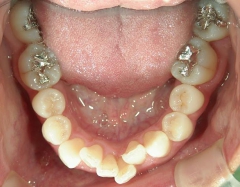

矯正歯科 治療後矯正歯科 プチワイヤー矯正 治療後矯正歯科(プチワイヤー矯正)治療後

矯正_灰色.pngno.41_8994_治療後_下.JPG矯正_灰色.png